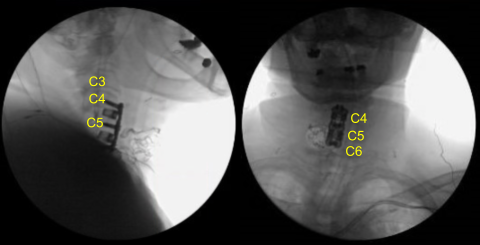

Los ensayos se utilizaron para seleccionar un espaciador intersomático de titanio lordótico de 7 mm que se llenó con autoinjerto morselizado y aloinjerto y se apisonó suavemente en los interespacios C4-5 y C5-6 con un mazo en la posición correcta. Se retiraron los pines Caspar. El defecto óseo fue encerado.

La PA y la fluoroscopia lateral mostraron un posicionamiento correcto. Los potenciales evocados motores mostraron una ligera disminución de la amplitud en el C5-6 derecho. La instrumentación fue entonces retirada. El espacio de instrumentación se limpió y se regó al ras.

La fluoroscopia mostró el tamaño y la posición correctos, por lo que se aseguró con seis tornillos de titanio de 14 mm decorticados con un taladro eléctrico de mano de 12 mm. La PA y la fluoroscopia lateral mostraron buen posicionamiento. Todos los tornillos se apretaron finalmente utilizando un dispositivo integrado en la placa.